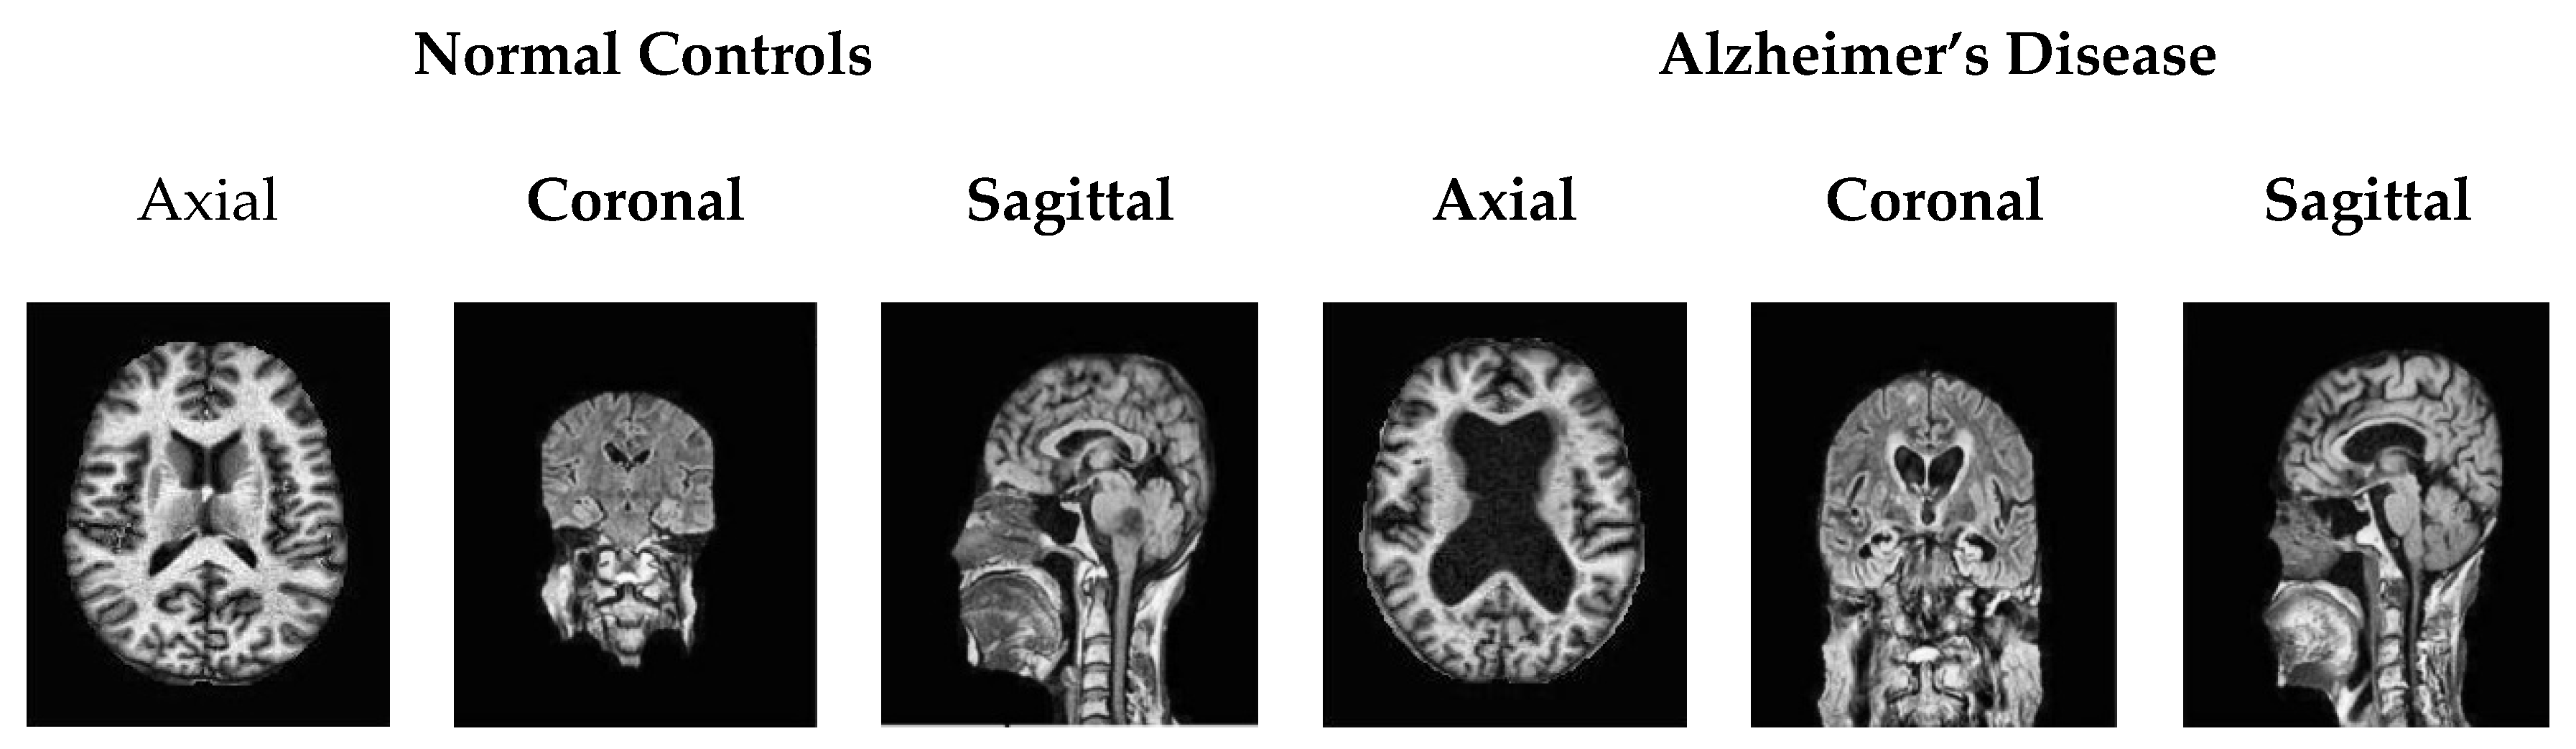

3.1. Dataset Availability